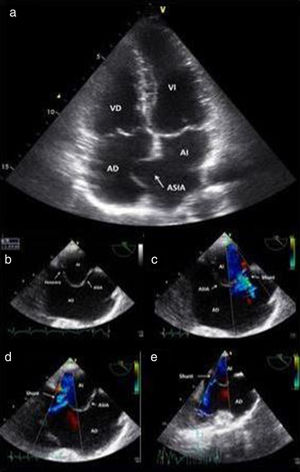

El ecocardiograma transtorácico y el ecocardiograma transesofágico mostraron leve dilatación del ventrículo derecho con función sistólica conservada, insuficiencia tricuspídea leve, aneurisma del septo interauricular y 3 shunts de izquierda a derecha, compatibles con comunicación interauricular secundaria a DSIA multifenestrado (fig. 3).